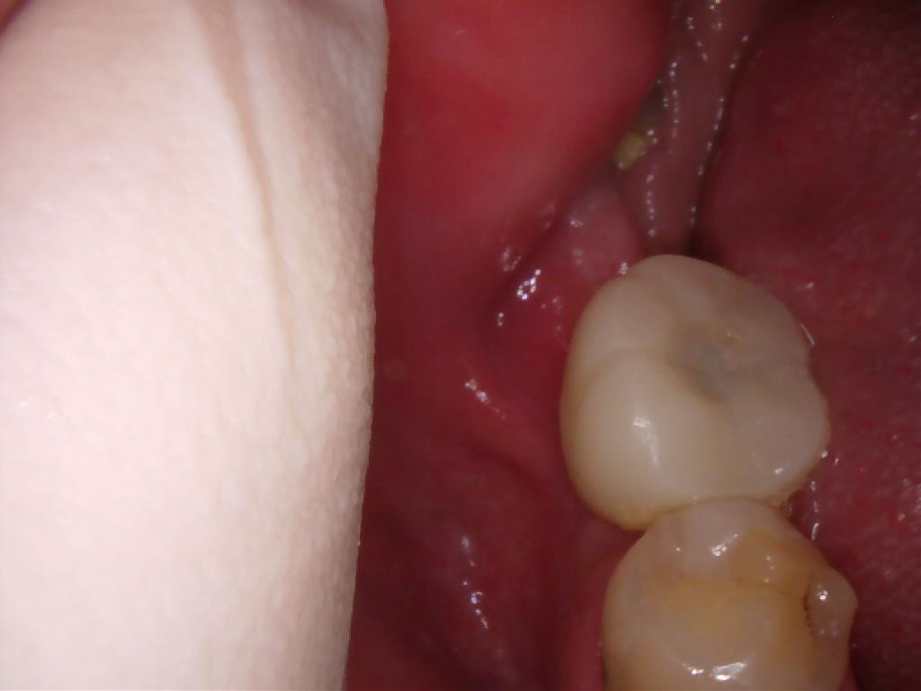

治療後

-

レントゲン写真

- 治療名称

- 右下56番パーシャルデンチャー部のインプラント治療

- 患者の症状

- 右下56番にパーシャルデンチャーを装着しており機能及び審美的に問題を抱えている。

- 治療内容

- まず、CT撮影による精密な骨の分析・治療計画を立てガイドを使いインプラント埋入しインプラントが骨と結合するのを待つ間に仮の歯を入れます。その後本歯を作成して装着しました。

- 治療期間・回数

- インプラント埋入からジルコニアセットまで三か月半

- 費用

※自由診療となります - ■総額:¥660,000(税込み) ■内訳:埋入(ガイド込み)¥200,000×2、仮歯¥20,000×2、被せ物¥80,000×2

- リスク・副作用

- ・術後の腫れ・痛み・出血 ・感染(インプラント周囲炎) ・インプラントの脱落 ・神経損傷によるしびれ ・破損・ゆるみ